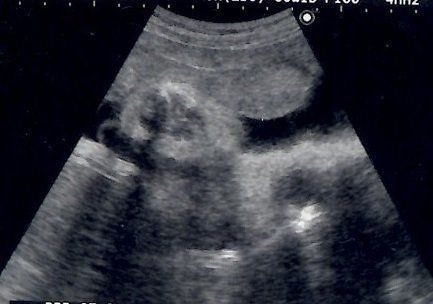

妊娠36週目のエコー写真 逆子発覚!

出産~子育ての体力作りのためのウォーキングに日々励んでいた頃、まさかの“逆子”が発覚!医師から「2週間後に帝王切開で出産します」と告げられて大あわてしました。病院から逆子を戻すための体操のやり方を教えてもらい、毎日必死にやり続けました。ある時、体操の後におなかの中でぐるん、と動くような気配を感じたので確認してもらったところ、無事逆子が戻っていました。